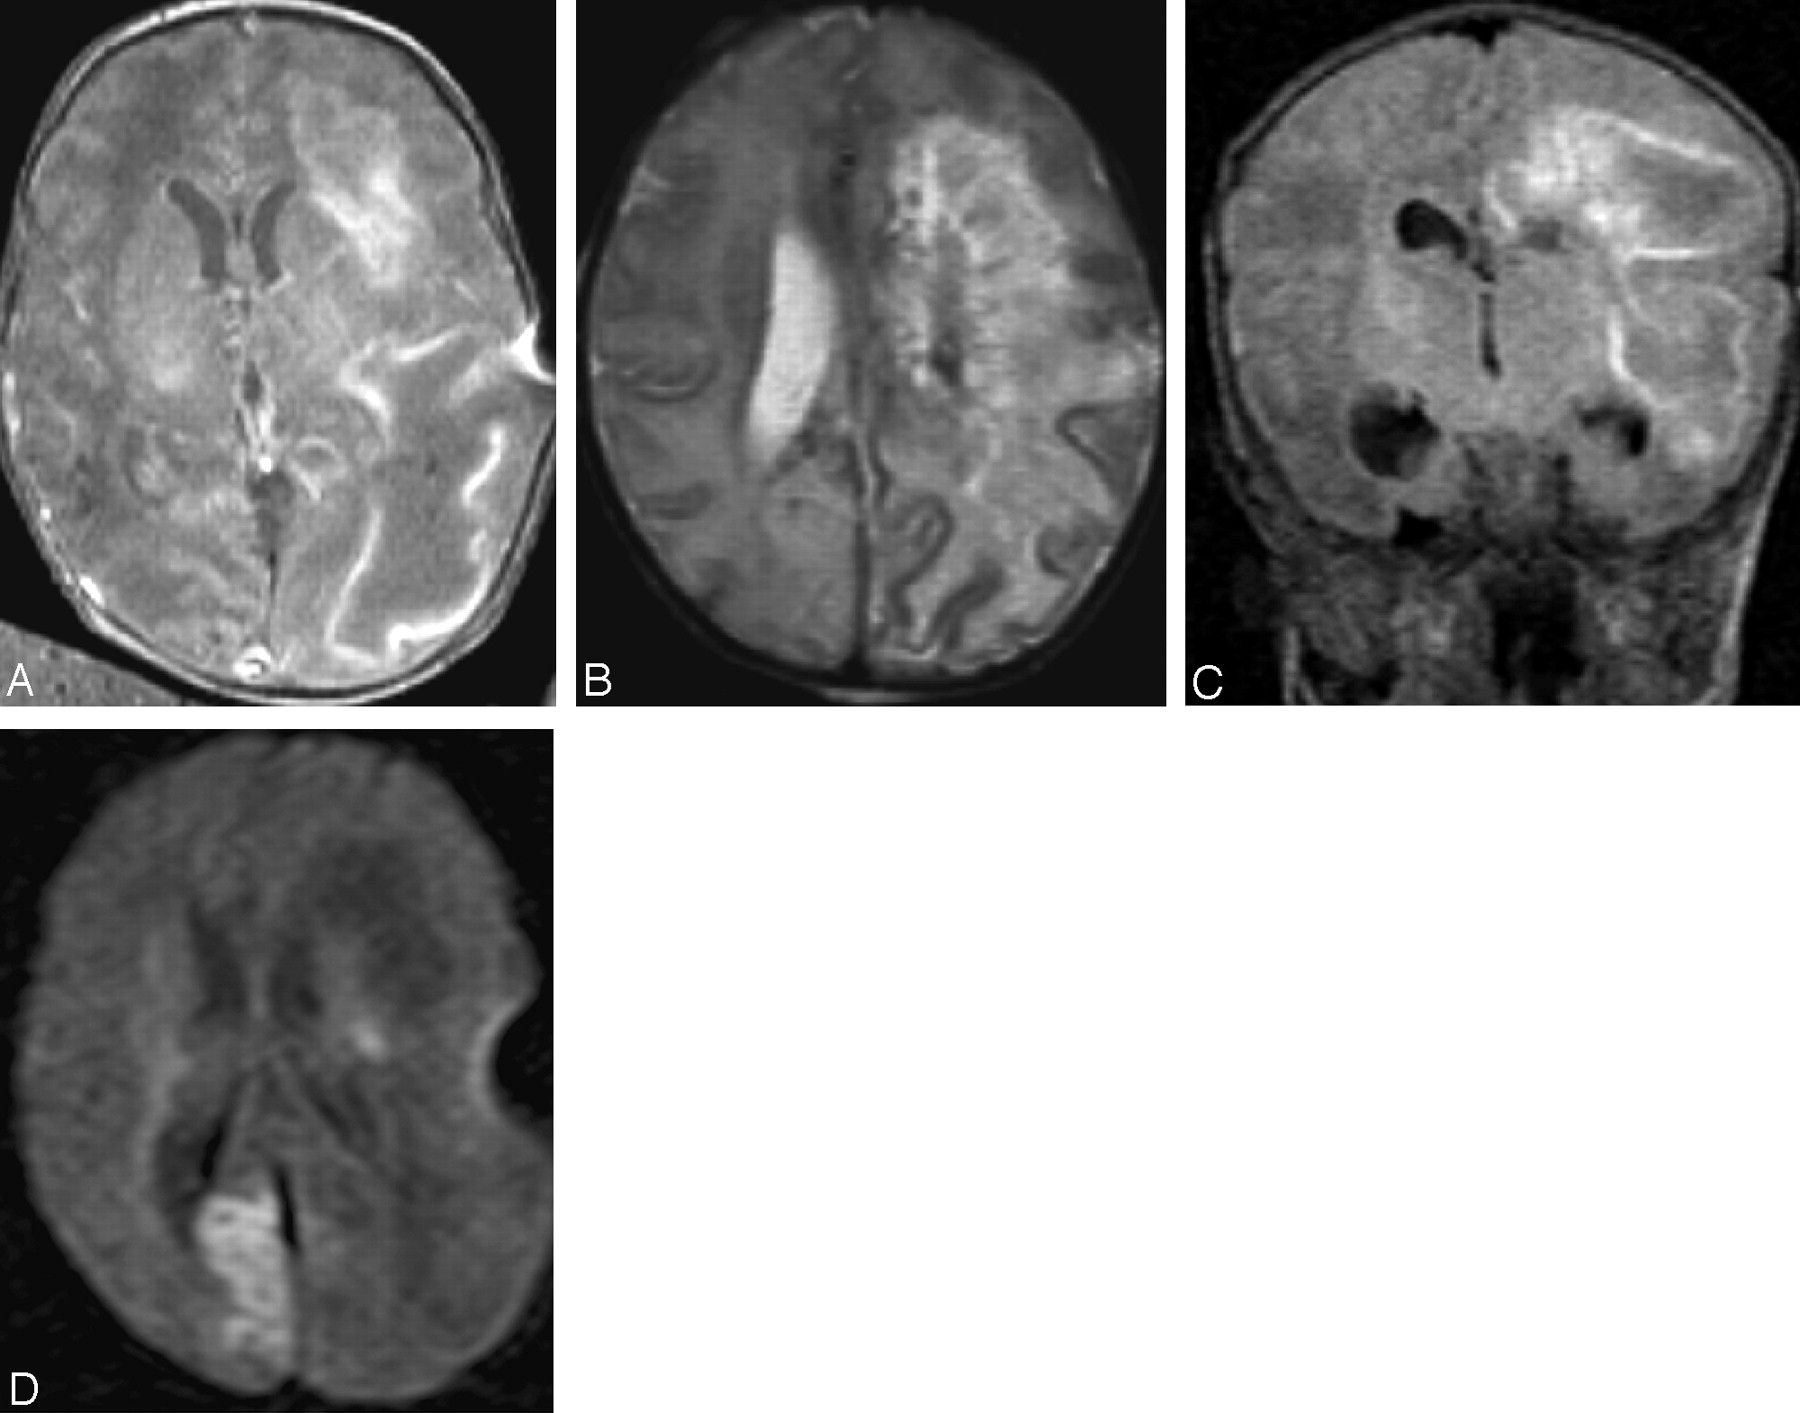

The T2-weighted MR images in the third infant (case 3) showed confluent hypointense areas in white matter indicative of massive hemorrhagic destruction in both hemispheres, in the areas seen with sonography (Fig 4A–C). These areas of destruction were not compatible with patterns seen in arterial as well as venous infarction. Superior sagittal, straight, and transverse sinuses were patent. Cortical sparing can be seen on MR images, though the right occipital lobe is subtlely abnormal on the T2-weighted images in Fig 4B. A rim enhancement around the ventricles was seen on the T1-weighted SE with gadolinium, which is indicative of ventriculitis. DWI showed an additional ischemic area at the calcarine cortex at the right side (Fig 4D).

Case 3. On day 15 axial T1-weighted SE (A), axial T2 TSE (B), and coronal FLAIR (C) images show hemorrhagic liquefactive necrosis of the left hemisphere (case 3). D, Diffusion-weighted image (TR, 1440 ms; TE, 146 ms; b = 756 mm2/s) shows restrictive diffusion in the calcarine area.